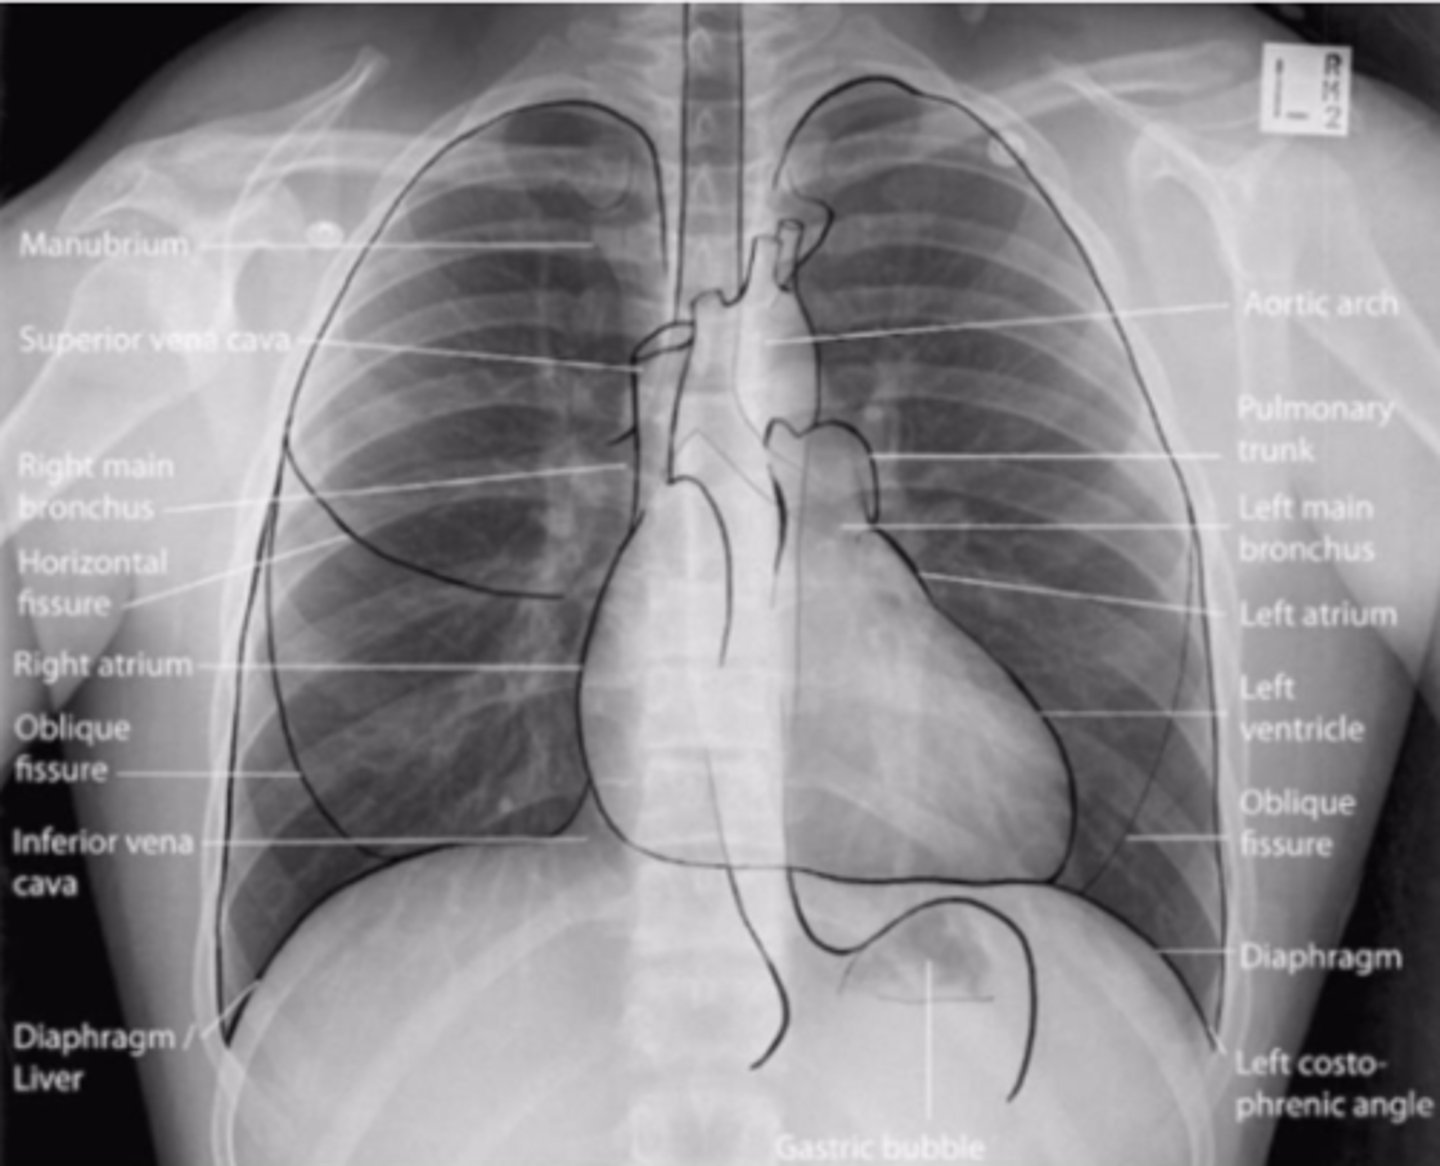

Radiographic anatomy

is the study of body structures that can be visualized with x-rays.